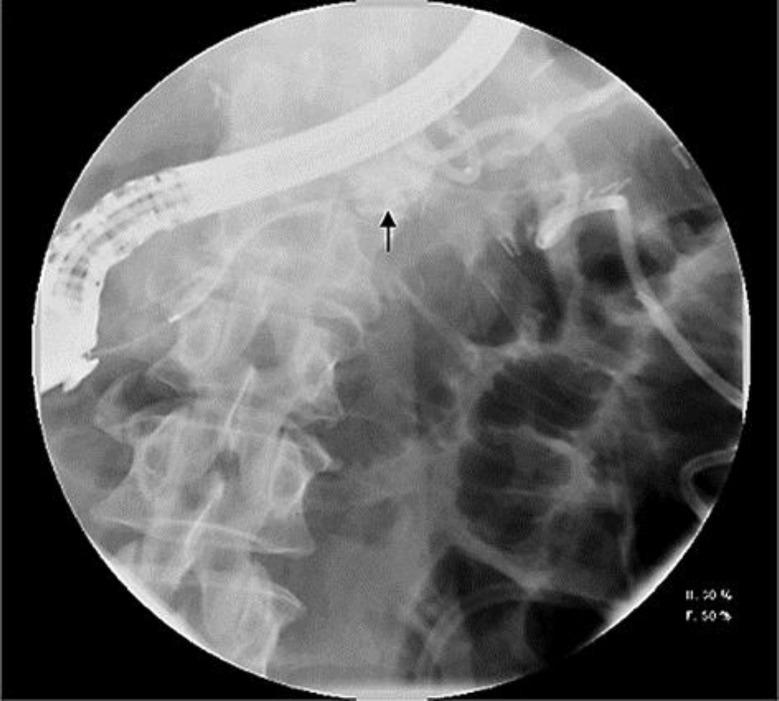

Pancreatic fistula is a known complication of distal pancreatectomy. Endotherapy with pancreatic duct stent placement and pancreatic sphincterotomy has been shown to be effective in its management; however, experience of endotherapy in the management of this complication has not been extensively reported from the United States. Preoperative endoscopic retrograde cholangiopancreatography (ERCP) with pancreatic stent placement has also been proposed to prevent this complication after distal pancreatectomy. In our cohort of 59 patients who underwent distal pancreatectomy, 13 (22%) developed a pancreatic fistula in the immediate postoperative period, of whom 8 (14%) patients (5 female, mean age 52 years) were referred for an ERCP because of ongoing symptoms related to the pancreatic fistula. The pancreatic fistula resolved in all patients after a median duration of 62 days from the index ERCP. The median number of ERCPs required to document resolution of the pancreatic fistula was 2. Although a sizeable percentage of patients develop a pancreatic fistula after distal pancreatectomy, only a small percentage of patients require ERCP for management of this complication. Given the high success rate of endotherapy in resolving pancreatic fistula and the fact that the majority of patients who undergo distal pancreatectomy never require an ERCP, performing ERCP for prophylactic pancreatic duct stent prior to distal pancreatectomy might not be necessary.

胰瘘是胰体尾切除术已知的并发症。胰管支架置入和胰管括约肌切开术的内镜治疗已被证明对其治疗有效;然而,美国尚未广泛报道内镜治疗该并发症的经验。术前内镜逆行胰胆管造影(ERCP)并放置胰管支架也被提议用于预防胰体尾切除术后的这种并发症。在我们的59例接受胰体尾切除术的患者队列中,13例(22%)在术后即刻发生了胰瘘,其中8例(14%)患者(5例女性,平均年龄52岁)因与胰瘘相关的持续症状而接受ERCP检查。自首次ERCP起,所有患者的胰瘘在中位时间62天后均得到解决。记录胰瘘解决所需的ERCP中位次数为2次。尽管相当比例的患者在胰体尾切除术后发生胰瘘,但只有一小部分患者需要ERCP来处理这种并发症。鉴于内镜治疗解决胰瘘的成功率很高,且大多数接受胰体尾切除术的患者从未需要ERCP,在胰体尾切除术前行ERCP预防性放置胰管支架可能没有必要。